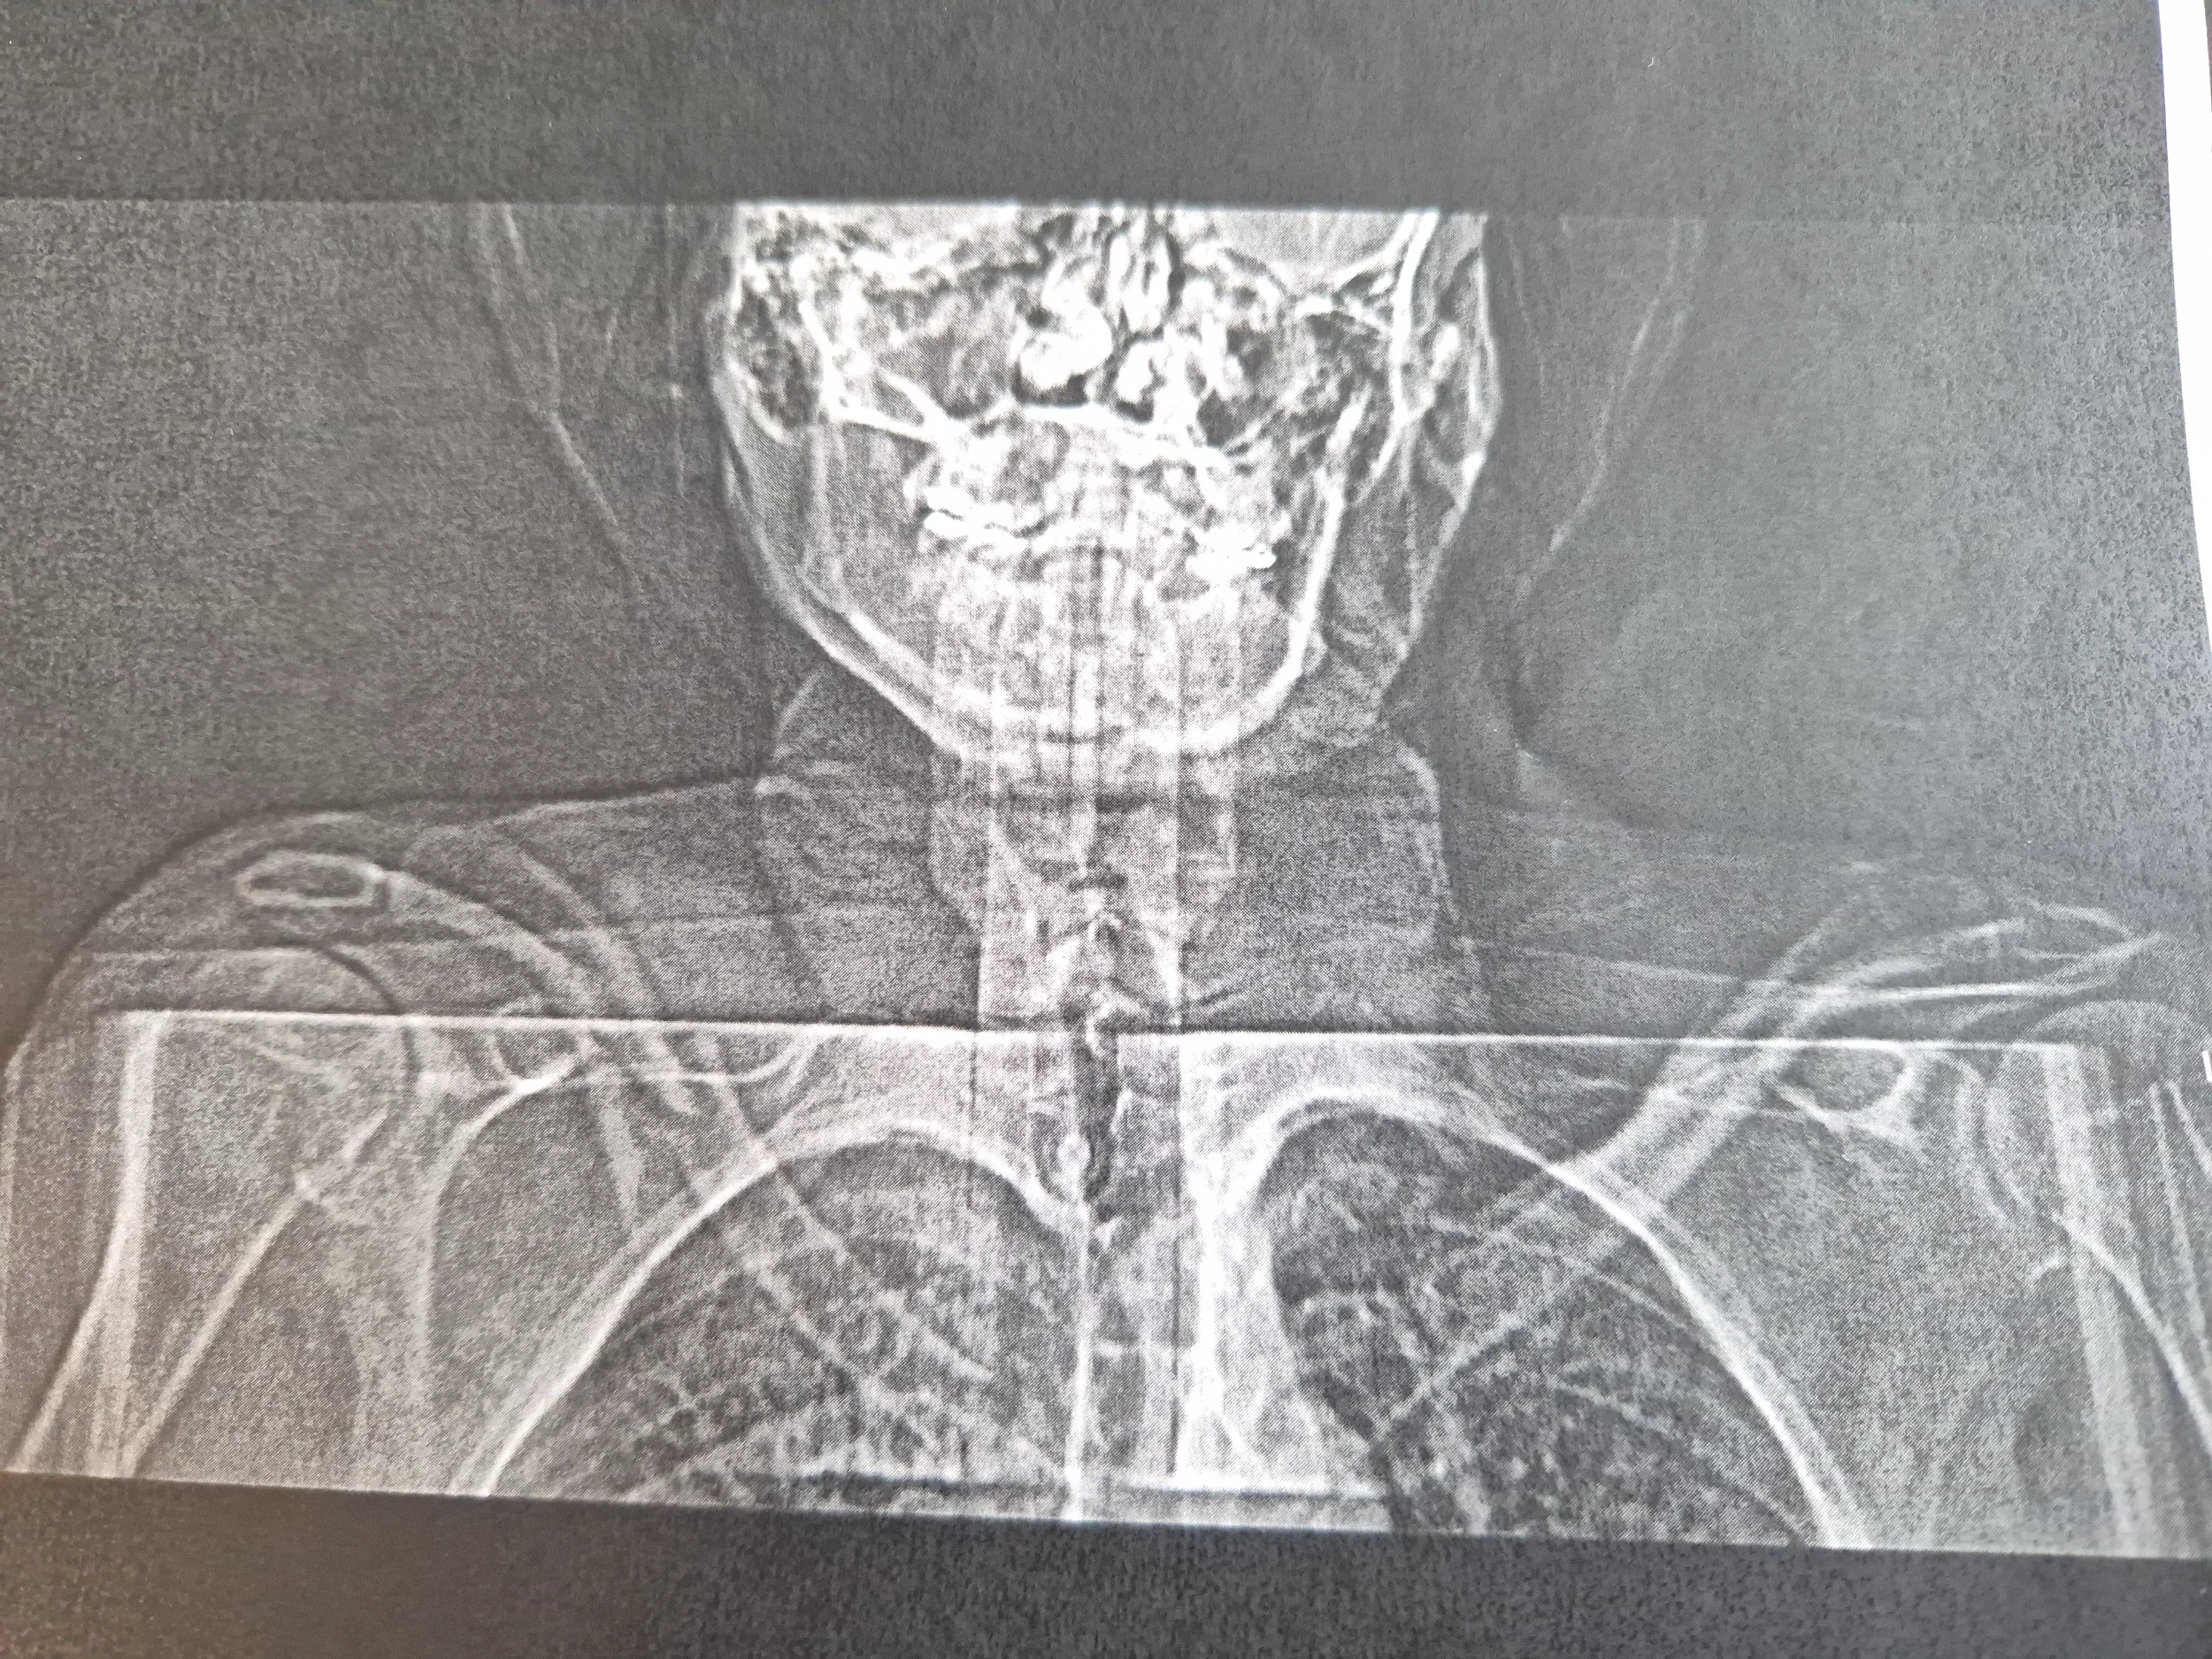

HIgh-sider på en cykelbana igår efter att jag förmodligen kört på en halvstor sten som gjorde att styret vreds 90 grader. Det var åtminstone vad han som låg bakom hade sett. Själv har jag inget minne från strax före vurpan till ca 30 minuter efter.

Förutom fraktur på höger nyckelben är det två frakturer i bäckenet och allmänt blåslagen och hjärnskakning. Frakturerna är stabila så ingen operation.

Lär ta ett antal månader för frakturläkning och rehab.😮‍💨